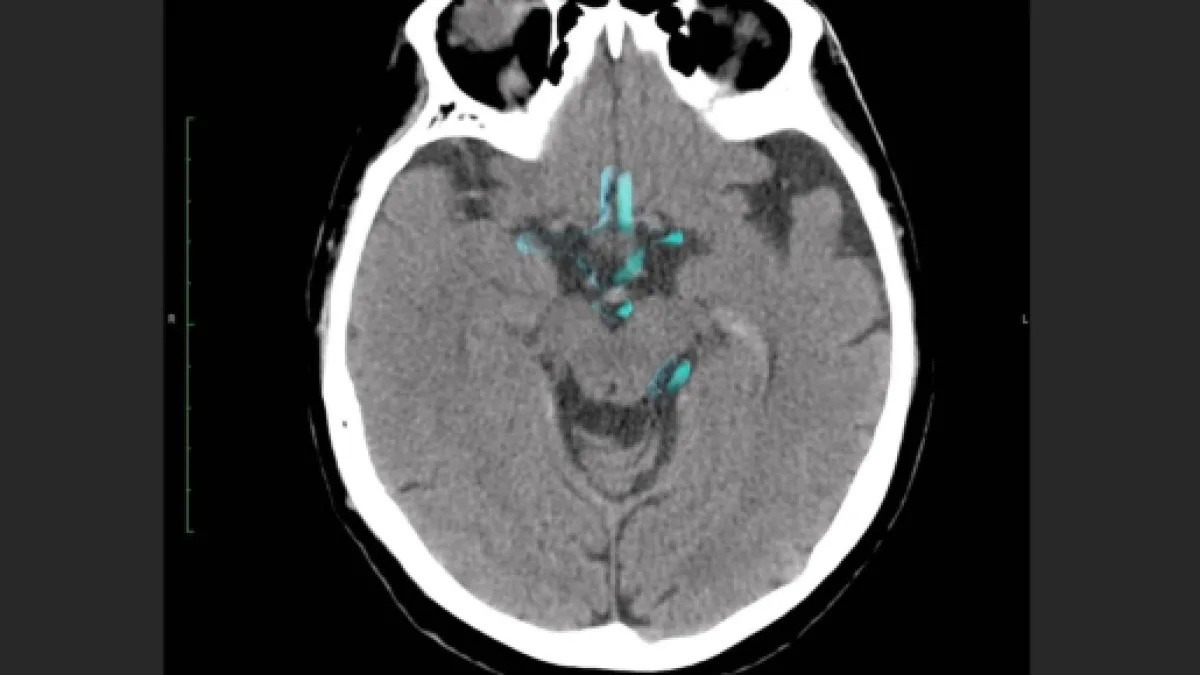

Pelos resultados de pesquisa obtidos e divulgados pela Revista Nature Neuroscience e utilizando-se da metodologia de pesquisa denominada "interação grupo por tempo", pode-se inferir que ocorria decrescimento em formação estrutural envolvendo a interação da região frontoparietal coligada a outras áreas do cérebro, como aquelas responsáveis pela atenção visual, dorsal, além de redes padrão e subcorticais.

Dessa forma, as ligações neuronais esperadas e necessárias à fase juvenil mostraram-se mais intensas (hiperconectividade), que do grupo neurotípicio no início do acompanhamento, mas decrescentes durante as próximas fases de acompanhamento (poda adaptativa).

O grupo neurotípico obteve aumento em intensidade na conectividade dessa interação-rede durante um longo-prazo em comparação ao grupo portador do Transtorno. Essa diferença temporal envolvendo a conectividade das áreas apresentadas, foi percebida também no gênero feminino e remete ao fato de que há diferenças de sintomatologias no Espectro no decorrer de um diagnóstico.

Sendo assim, o TEA "afeta o desenvolvimento da conectividade intra e inter-sistema do sistema frontoparietal na adolescência e no início da fase adulta", mas demonstrou-se que a "poda adptativa" é realizada ao fim da fase infantil e no início da adulta, possibilitando melhoria dos sintomas.